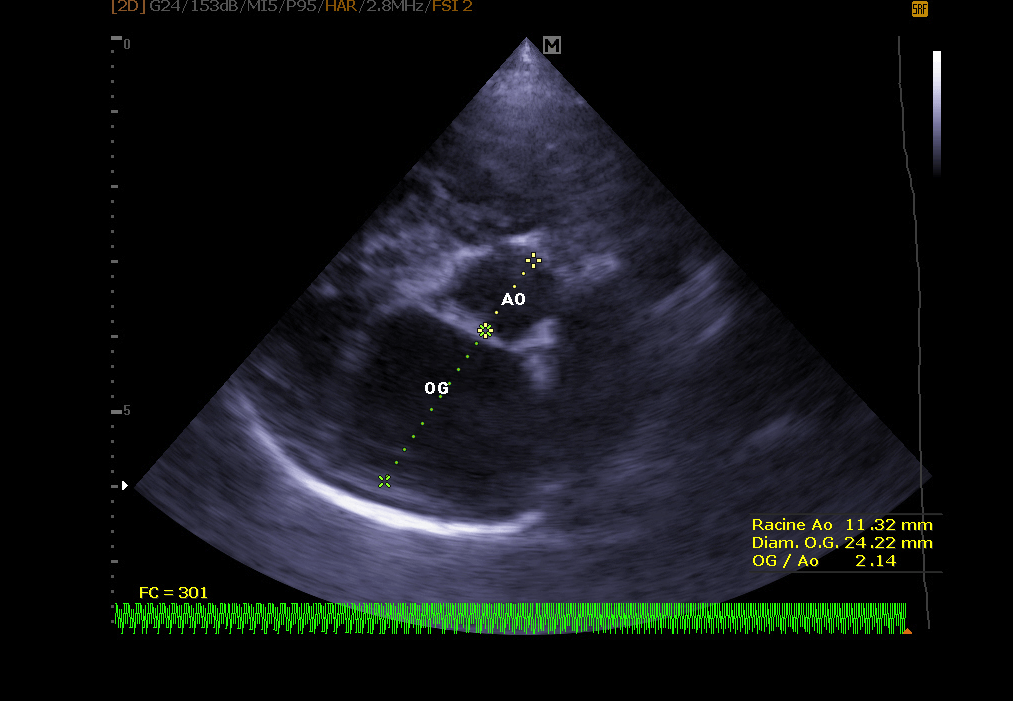

Echocardiography:

It makes it possible to visualize the different parts of the heart (walls, cavities, valves) and to identify any anomalies that prevent correct cardiac functioning. In case of heart failure, echocardiography also allows regular monitoring of cardiac morphology. It is then easier to readjust the treatment in place.